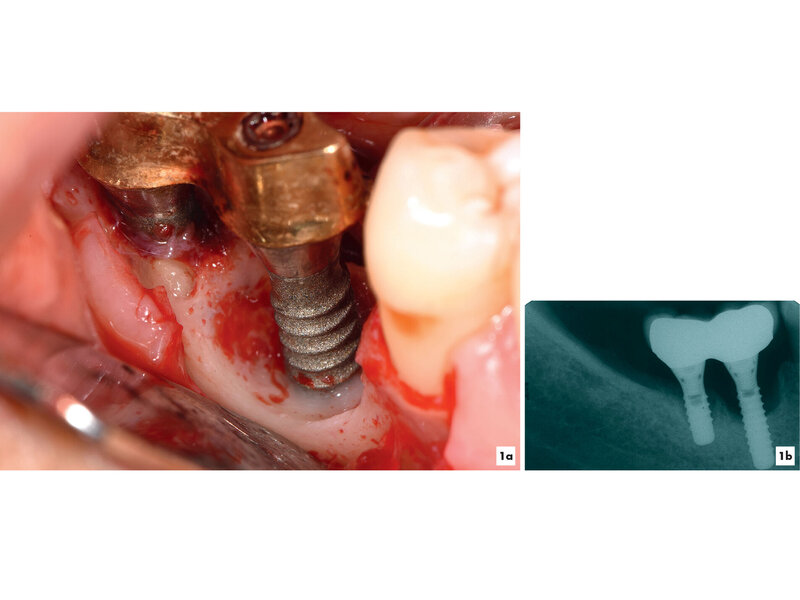

Kommt es jedoch zur Ausbildung einer Inflammation periimplantärer Gewebe ohne Knochenverlust, spricht man von einer periimplantären Mukositis. Wichtigstes Kennzeichen sind dabei die Blutung auf Sondierung und die Begrenzung der Entzündung auf das periimplantäre Saumepithel [Berglundh et al., 2018]. Breitet sich der pathologische Prozess in den Bereich des knöchernen Attachments aus, ist die Destruktion irreversibel und man spricht von einer Periimplantitis (Abbildung 1a). Zusätzlich zu den bereits genannten klinischen Kennzeichen kann man hier auch röntgenologisch den Knochenverlust feststellen, der mit erhöhten Sondierungstiefen und/oder Rezessionen einhergeht [Berglundh, 2019] (Abbildung 1b).